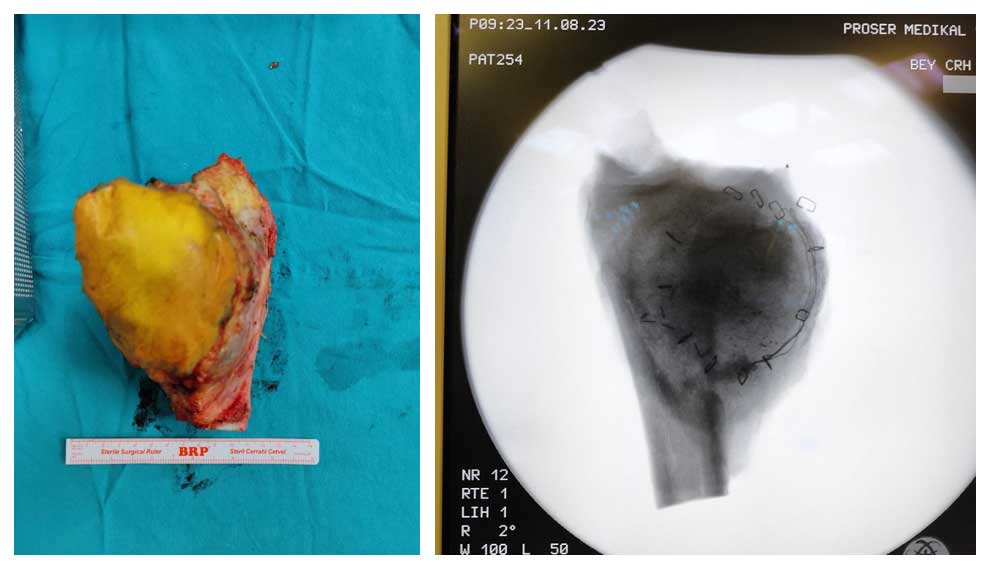

Ameliyat Esnası: Çıkarılan tümör dokusunun klinik ve skopi görüntüsü.